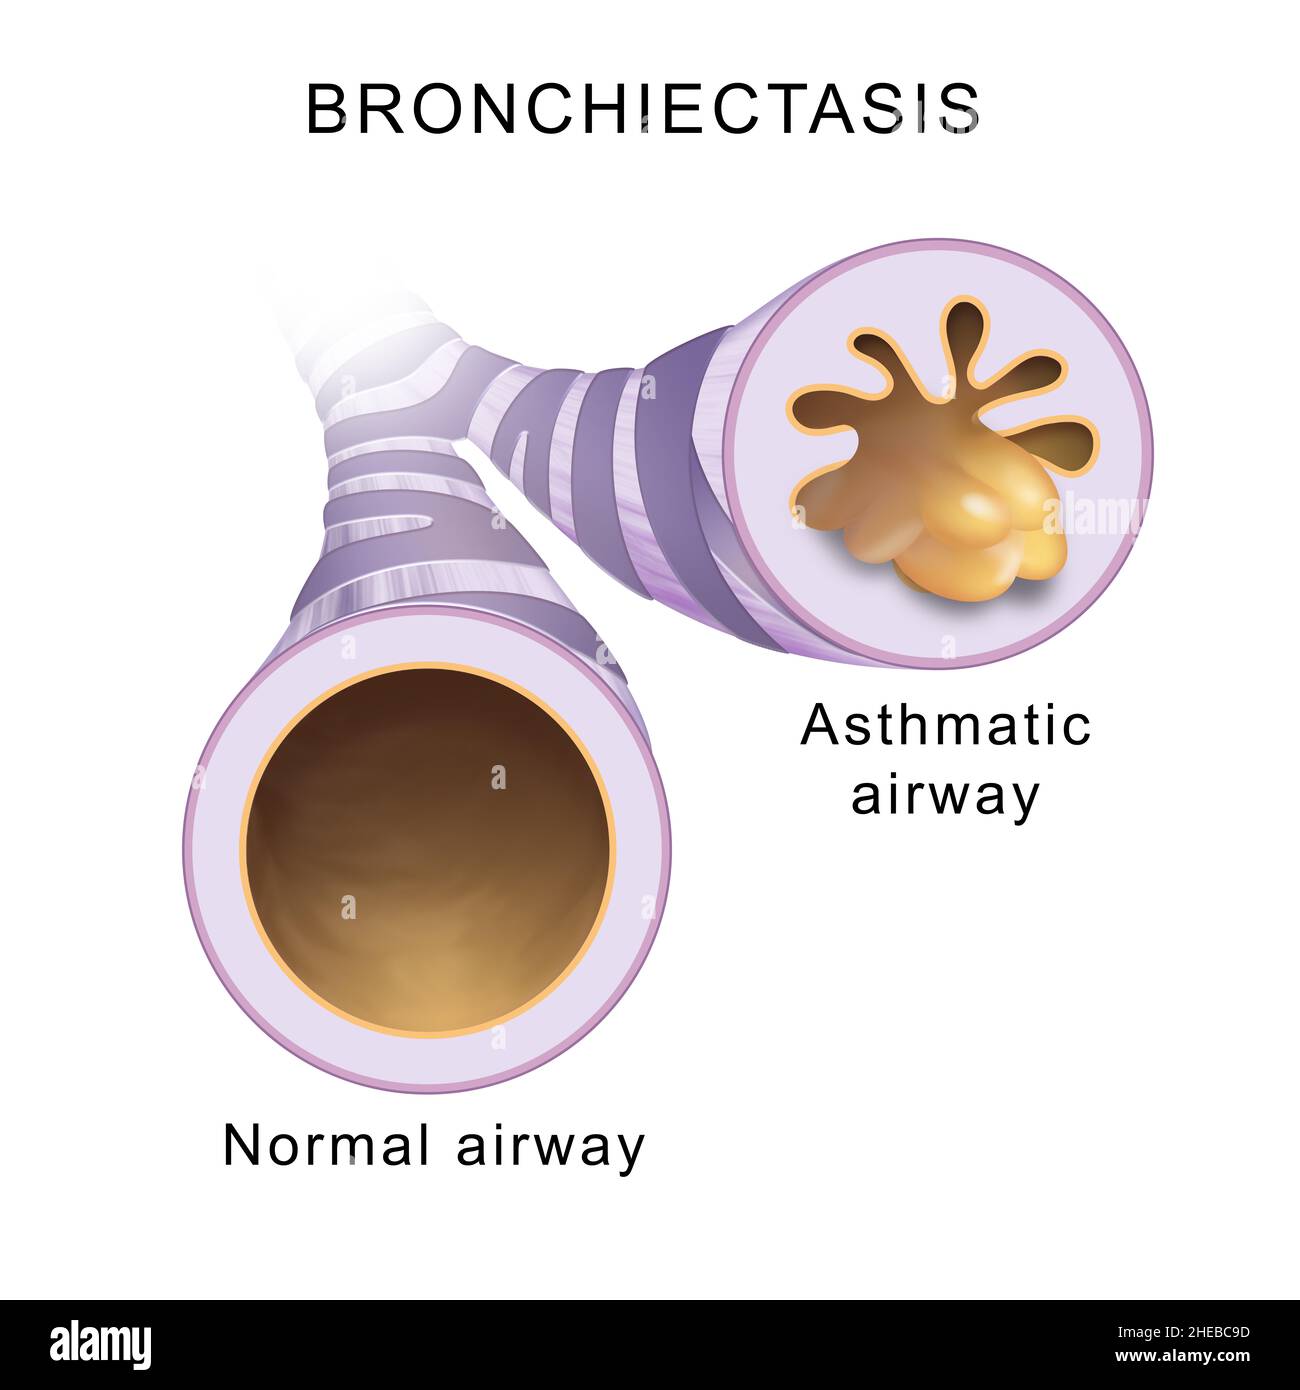

Bronchiectasis. Normal airway and asthmatic airway Stock Photohttps://www.alamy.com/image-license-details/?v=1https://www.alamy.com/bronchiectasis-normal-airway-and-asthmatic-airway-image456325897.html

Bronchiectasis. Normal airway and asthmatic airway Stock Photohttps://www.alamy.com/image-license-details/?v=1https://www.alamy.com/bronchiectasis-normal-airway-and-asthmatic-airway-image456325897.htmlRF2HEBC9D–Bronchiectasis. Normal airway and asthmatic airway